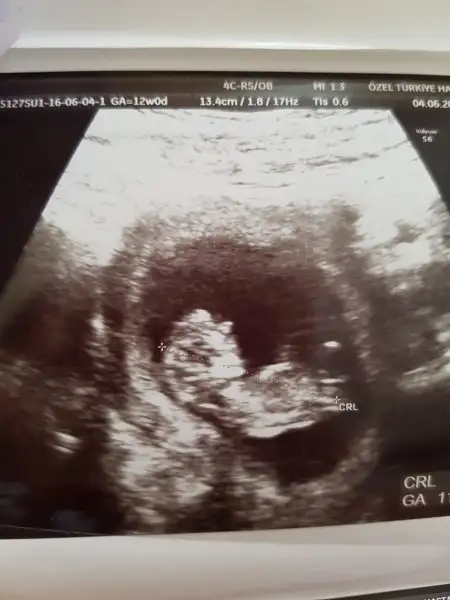

Nubtan anlayan teyzeleri yorum yapabilir mi 11 +6 dün ki ultrason resmimiz